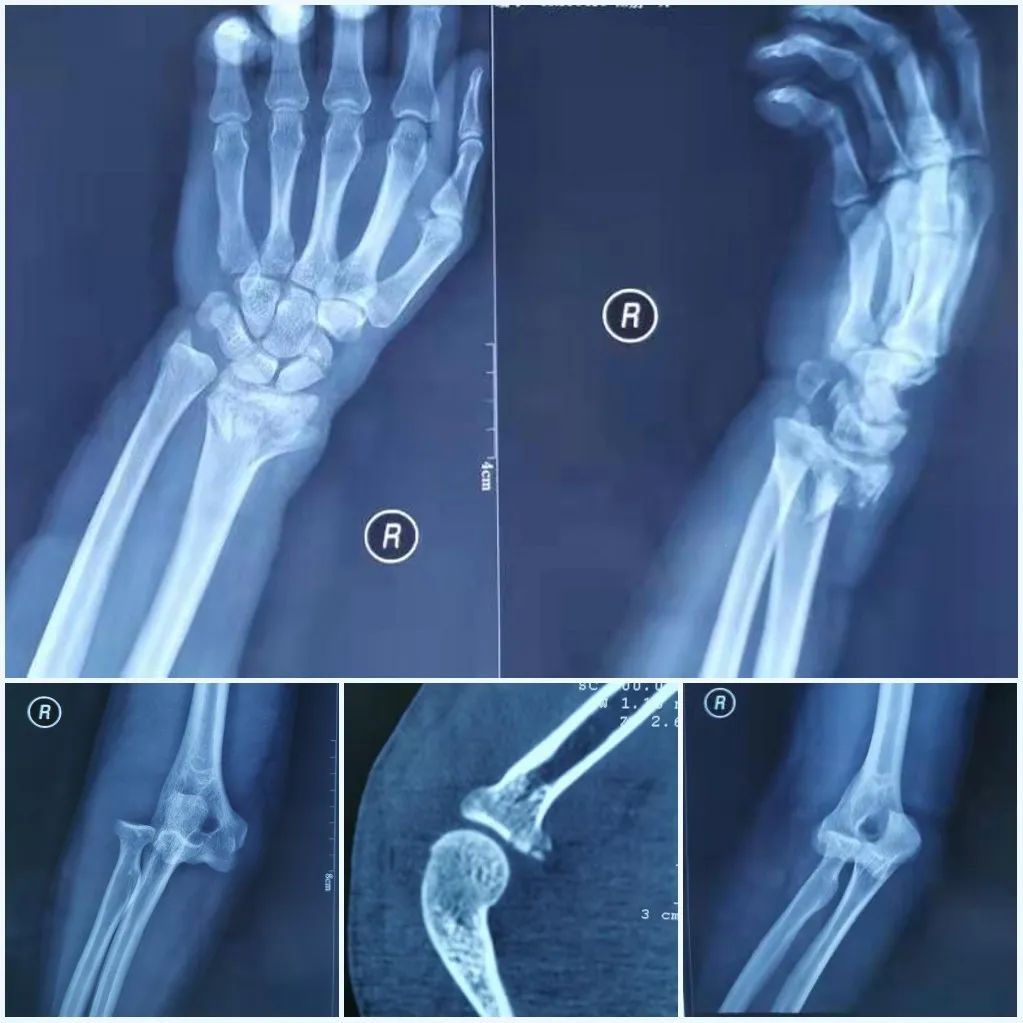

肘关节骨折脱位 我们该如何正确诊治 好医术早读文章 好医术 赋能医生守护生命

子どもが肘を骨折して手術。 治療期間はどのくらいだった? 18年12月2日 / 19年2月1日 スポンサーリンク 子供が肘を骨折し、手術しました。 肘の完治までどのようなスケ電話予約可 肘頭骨折、尺骨近位端骨折 肘の骨折です。 肘の後ろに出っ張っている骨を肘頭をいいます。 この骨には肘を伸ばすための上腕三頭筋がついています。 また肘関節内の病因 播报 本病由直接外力引起的骨折很少见。 常见的是肘关节伸直位摔倒,手掌着地,外力使桡骨头在外翻位与肱骨小头撞击而产生骨折。 常合并肱骨小头损伤与内侧副韧带损伤。 多见于成年人且容

骨折の治癒過程は炎症期、修復期、改変期(再造形期)の3ステージに分類されます。 それでは一つ一つのステージやかかる期間について解説していきます。 炎症期 骨折が起きると骨 以下は、70代女性の肘の骨折の受傷時のレントゲンです。 転位が大きく、手術を行いました。 術後のレントゲンです。 正常な位置に整復されている事がわかると思います。 手術翌日よ